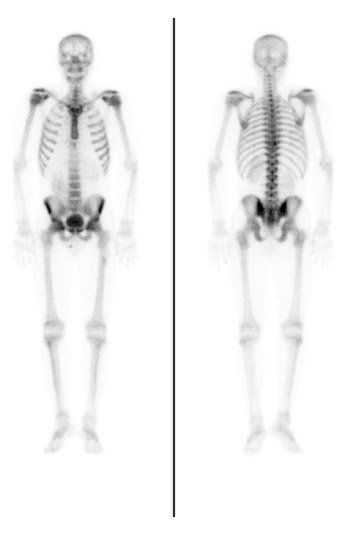

Binnen de nucleaire geneeskunde wordt gebruik gemaakt van het verval van radioactieve isotopen voor zowel diagnostische als therapeutische doeleinden.